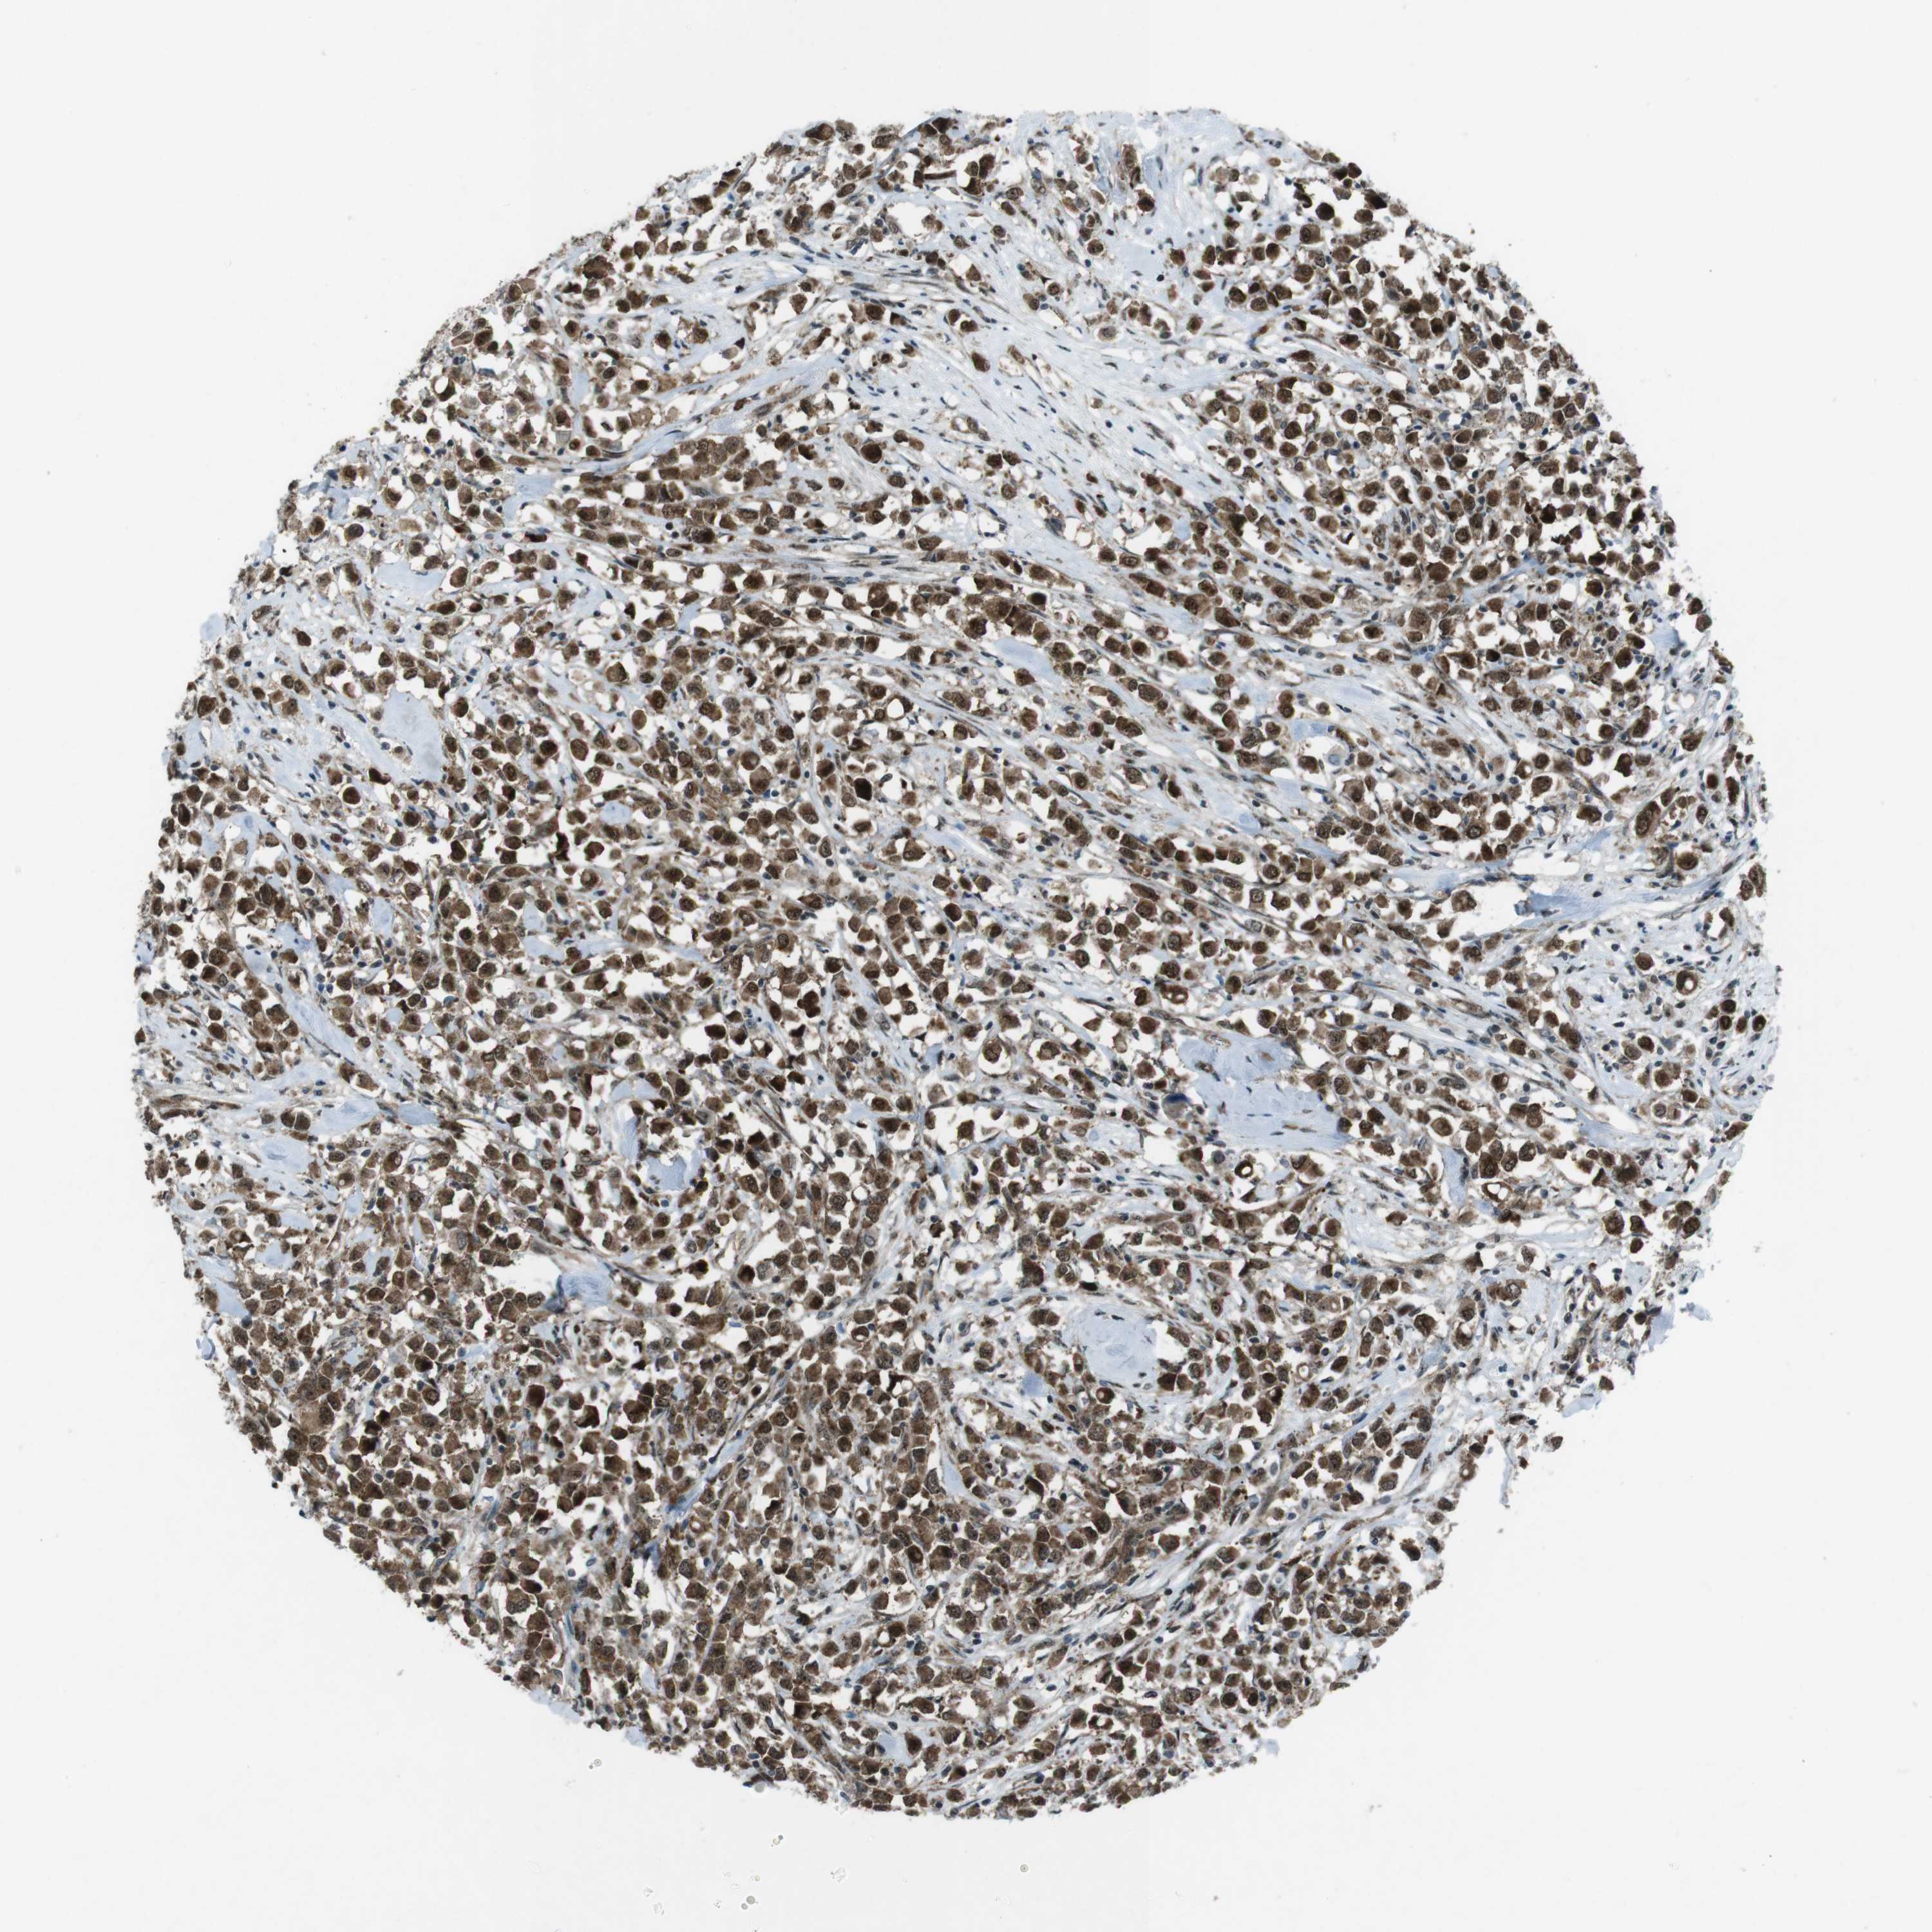

CANCER BREAST CANCER Show tissue menu

BRCA TCGA BRCA VALIDATION PROTEIN EXPRESSION